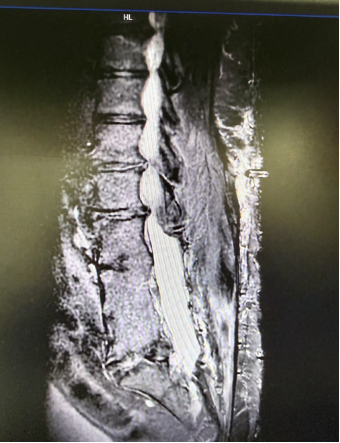

患者术前MRI

接诊后,疼痛科团队对患者进行了系统、全面的评估,结合其病史、临床表现及影像学检查结果,组织多学科会诊讨论。团队发现,T先生患者手术区域局部解剖结构明显异常,存在术后瘢痕粘连及椎管极度狭窄等改变,大大增加了电极置入的技术难度与操作风险。经多学科团队反复讨论并充分告知患者诊疗方案后,决定短时程脊髓电刺激作为疗效测试和安全性评估手段,后续根据镇痛效果和耐受情况,审慎评估是否行永久性电刺激系统植入,并据此制定了周密的个体化手术方案。